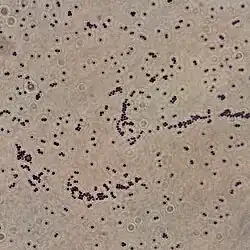

| Gram stain of a Gram positive S. saprophyticus sample suspension, lab cultured on Tryptic Soy agar (TSA) | |

Staphylococcus saprophyticus is identified as belonging to the genus Staphylococcus using the Gram stain and catalase test. It is identitified as a species of coagulase-negative staphylococci (CoNS) using the coagulase test. Lastly, S. saprophyticus is differentiated from S. epidermidis, another species of pathogenic CoNS, by testing for susceptibility to the antibiotic novobiocin. S. saprophyticus is novobiocin-resistant, whereas S. epidermidis is novobiocin-sensitive.[3]